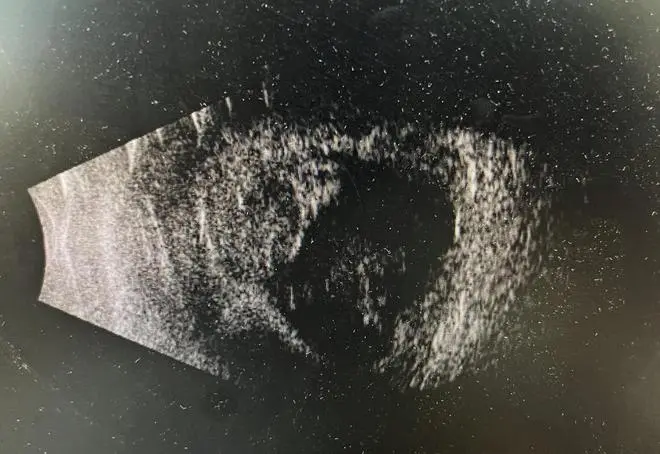

(B超显示患者玻璃体积血)

经查,张先生右眼眼球破裂,前房有大量积血,需要先通过手术对伤眼进行清创和探查,将受损的眼组织进行缝合与复位,保住眼球,再根据情况考虑能否做第二次手术找回视力。